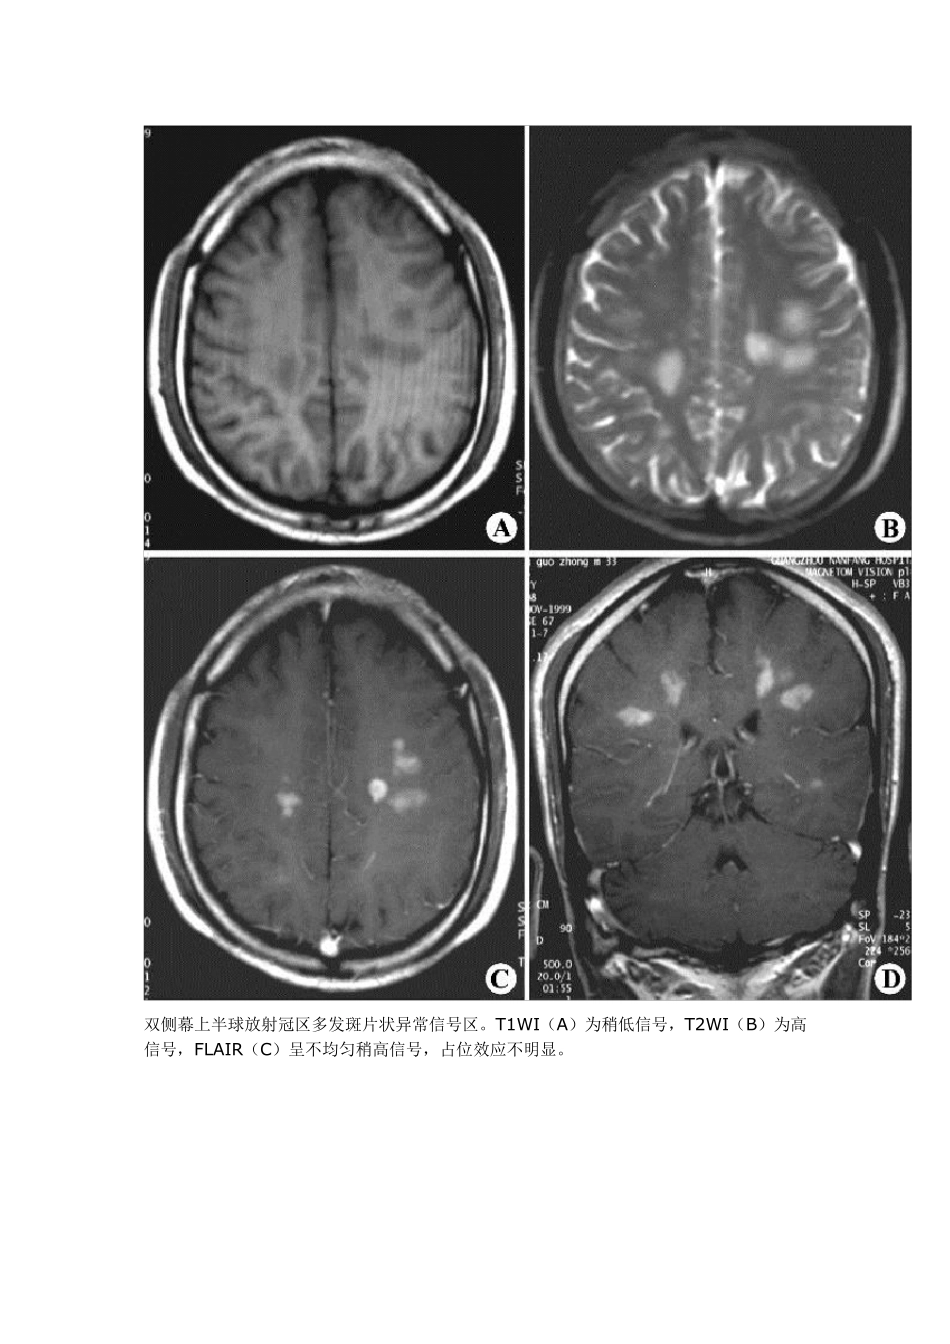

多灶性脱髓鞘: 1.多发硬化(Mu ltiple Sclerosis ,MS):中枢神经系统脱髓鞘疾病中最常见的一种类型,患者脑和脊髓内发生多灶性脱髓鞘斑块为其主要表现。 1.1 病理:病灶主要位于脑和脊髓的白质内,呈弥散分布。大脑半球大体观可正常,部分人有脑回轻度萎缩及脑沟增宽;切面可见大小不等的软化坏死灶和边缘清楚的灰色斑块,以侧脑室周围和小脑多见。显微镜检查:早期 病灶区髓鞘崩解,局部水肿,血管周围有淋巴细胞、浆细胞浸润等炎症反应。中期随髓鞘崩解产物被吞噬细胞逐渐清除,形成斑点状软化坏死灶,可见格子细胞形成 和轴索消失。晚期病灶区有胶质细胞与星形细胞增生,网状与胶原纤维增生,形成边界清楚的灰色斑块,直径一般在 0.1cm ~4.5cm 。病灶可新旧并存。重 症、晚期患者可见脑室扩大,脑回变平,脑沟增宽和脊髓变细等脑脊髓萎缩改变。偶尔MS 可伴胶质瘤,肿瘤起源于多发硬化的斑块。 1.2 影像学:MRIT1 加权像见多发斑点状低信号病灶,通常与侧脑室壁垂直排列,与脑室周围白质内小血管的走行方向一致。陈旧性斑块呈等信号。由于多发硬化是少突神经胶质-血管髓磷脂复合疾病,因此有5%者,皮质和基底节亦受累,半卵圆中心的病灶可有占位效应。脊髓病灶呈长 条形,与脊髓长轴走行一致,一般脊髓不增粗。T2 加权像病灶呈高信号,边缘清晰。质子密度加权像有利于显示靠近脑室边缘、脑干及小脑MS 病灶。Gd- DTPA增强扫描 T1 加权像急性脱髓鞘病灶强化,陈旧病灶无强化。 MRI 可判断 MS 的分期:MRI显示病灶大小不变、病灶缩小或数目减少,则提示为缓解期;若病灶增大或数目增多,则提示病情加重。MRI 还可用来随访治疗效果。 MRI 平扫示双侧侧脑室周围及深部脑白质多发斑片状异常信号区,T1WI(A、B)呈低信号,T2WI(C、D)呈高信号,未见占位效应 MRI 平扫示双侧半卵圆区多发斑片状异常信号区,呈长T1(A)和长T2(B)改变;增强扫描(C、D)病变明显强化 双侧幕上半球放射冠区多发斑片状异常信号区。T1W I(A)为稍低信号,T2W I(B)为高信号,FLAIR(C)呈不均匀稍高信号,占位效应不明显。 肿块样的ms,但较之肿瘤水肿轻,和对白质压迫的作用。 1.3MS 影像学鉴别诊断: 1.3.1 皮层下动脉硬化性脑病(Binsw anger 病):Binsw anger 病与高血压有关,对长期高血压和进行性痴呆的患者,结合脑MRI 表现可诊断此病.为老年人在脑动脉硬化基础上,大脑半球白质弥漫性脱髓鞘性脑病。主要累及侧脑...